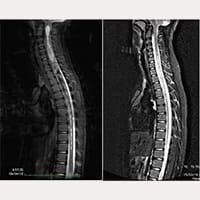

梅拉妮的核磁共振追踪

终丝手术术前

终丝手术术后

但梅拉妮的情况开始恶化了,她变得常常哭,她也因为疼痛常把身体弯起来,在2008年3月,我要求医院再给她拍第三次的核磁共振,结果证实她在颈4到胸7有脊髓空洞。

过了一星期后,医生们让她出院了,我们也回到了古比奥,但梅拉妮的身体还是一直都很不好,她坐着的时候身体还会失去平衡,后来我们又给她拍了新的核磁共振,结果发现她的脊髓空洞居然扩大到从颈1到胸11都有。